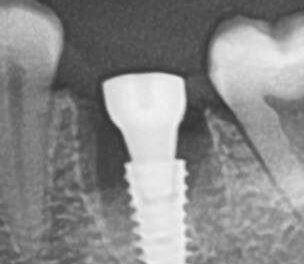

Специализация: терапия(эндодонтия), ортопедия, имплантология.